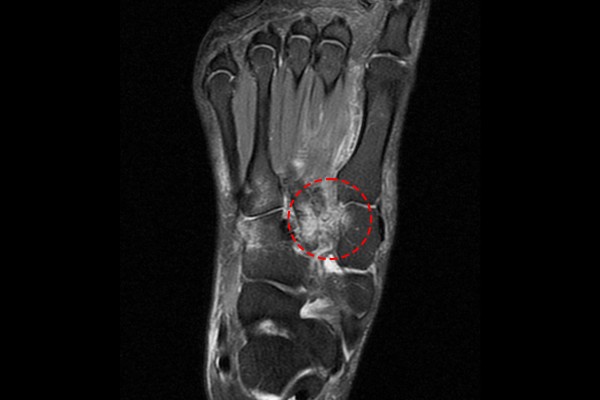

환자분의 자세한 발 상태 확인을 위한 MRI 검사 결과, 리스프랑 관절부 인대가 손상되어 까맣게 보여야할 인대가 보이지 않고, 하얀 신호변화만이 확인됩니다. 신체검진, X-RAY, MRI 검사 결과를 종합하여 우측 발 리스프랑 인대 손상(내측 쐐기골-제2 중족골간 인대) 파열(Lisfranc ligament injury foot Rt)을 진단하였습니다.